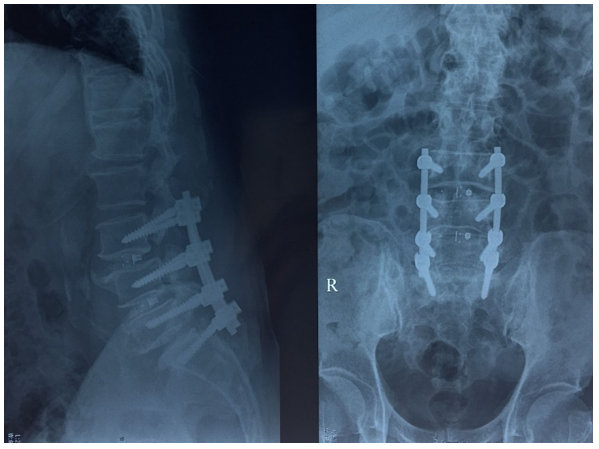

Hình 3. Xquang cột sống thắt lưng sau phẫu thuật 1 tháng. Phương tiện kết hợp xương L3, L4, L5, S1

Hình 2. Xquang cột sống thắt lưng sau phẫu thuật 3 ngày. Phương tiện kết hợp xương L3, L4, L5, S1.